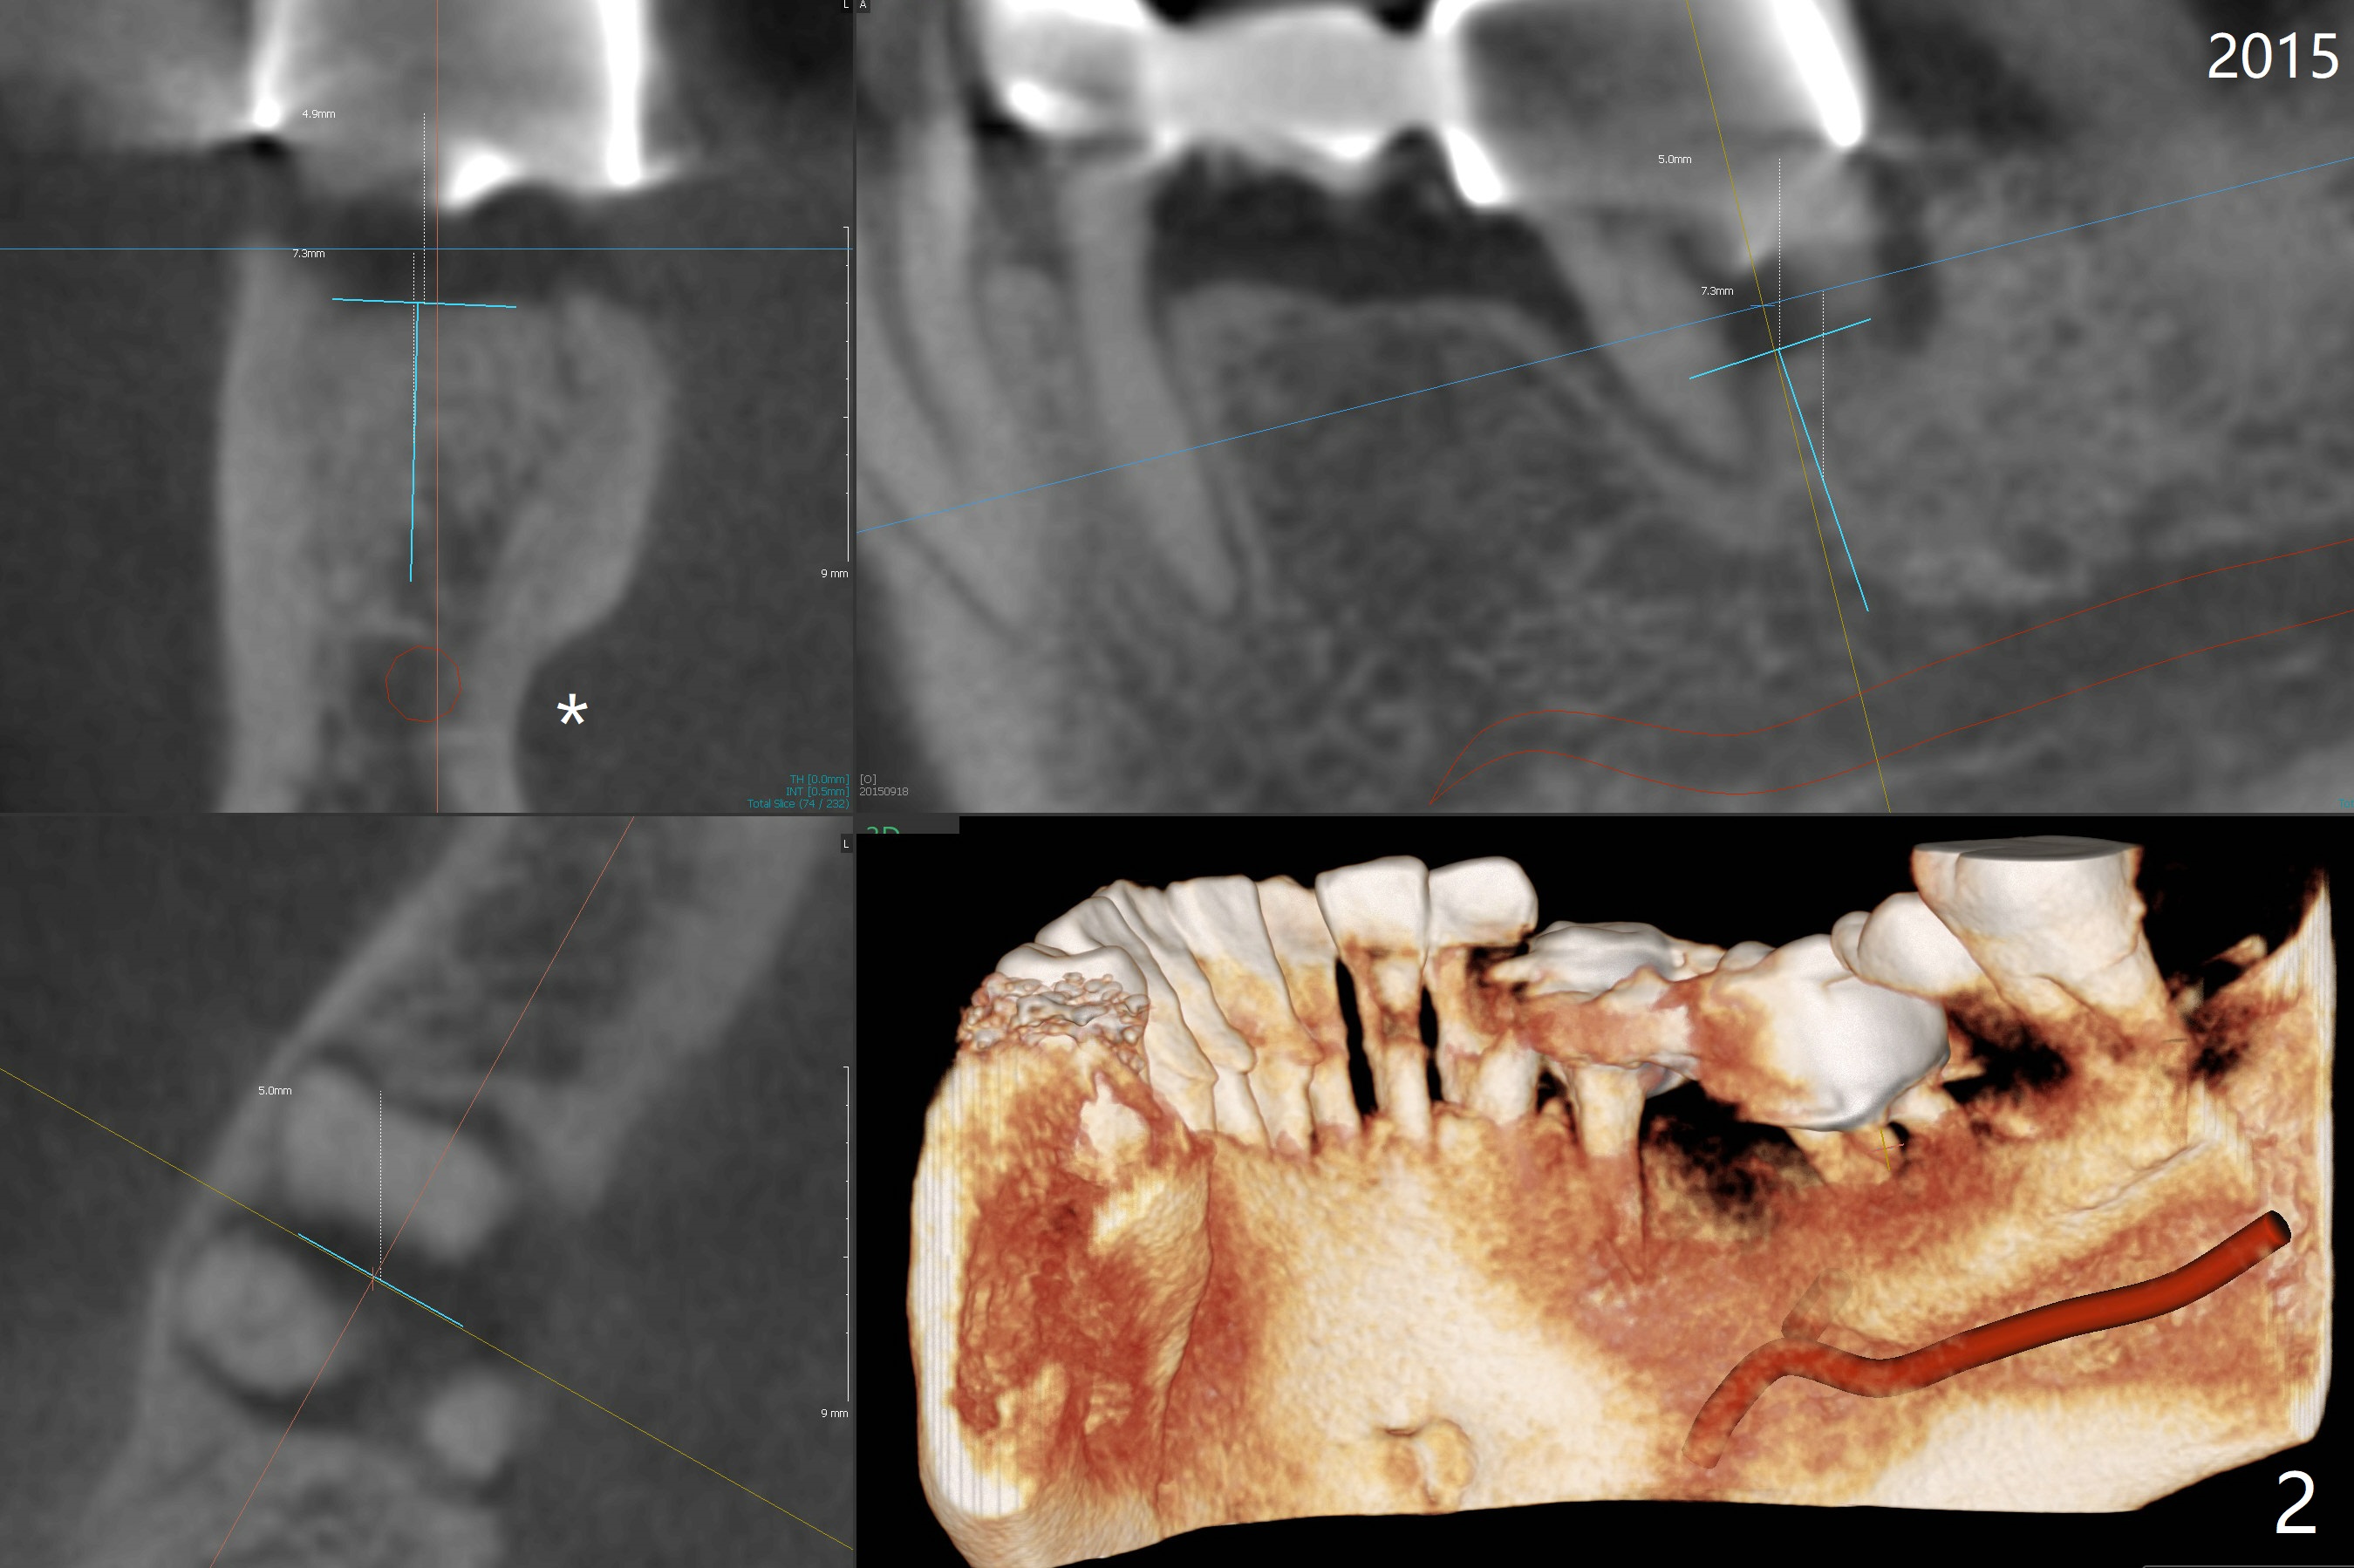

A 55-year-old man had #30 extracted and #29 pontic removed ~ 3 months ago (Fig.1,2). Short implants are to be placed (4.5x8.5 and 5x7.3 mm) with guide. Pay attention to the submandibular fossa (Fig.2 *) as related to the site of #30. New CT (Fig.3,4 (2018)) shows that implants will be 4x7.3 and 5x7.3 mm.